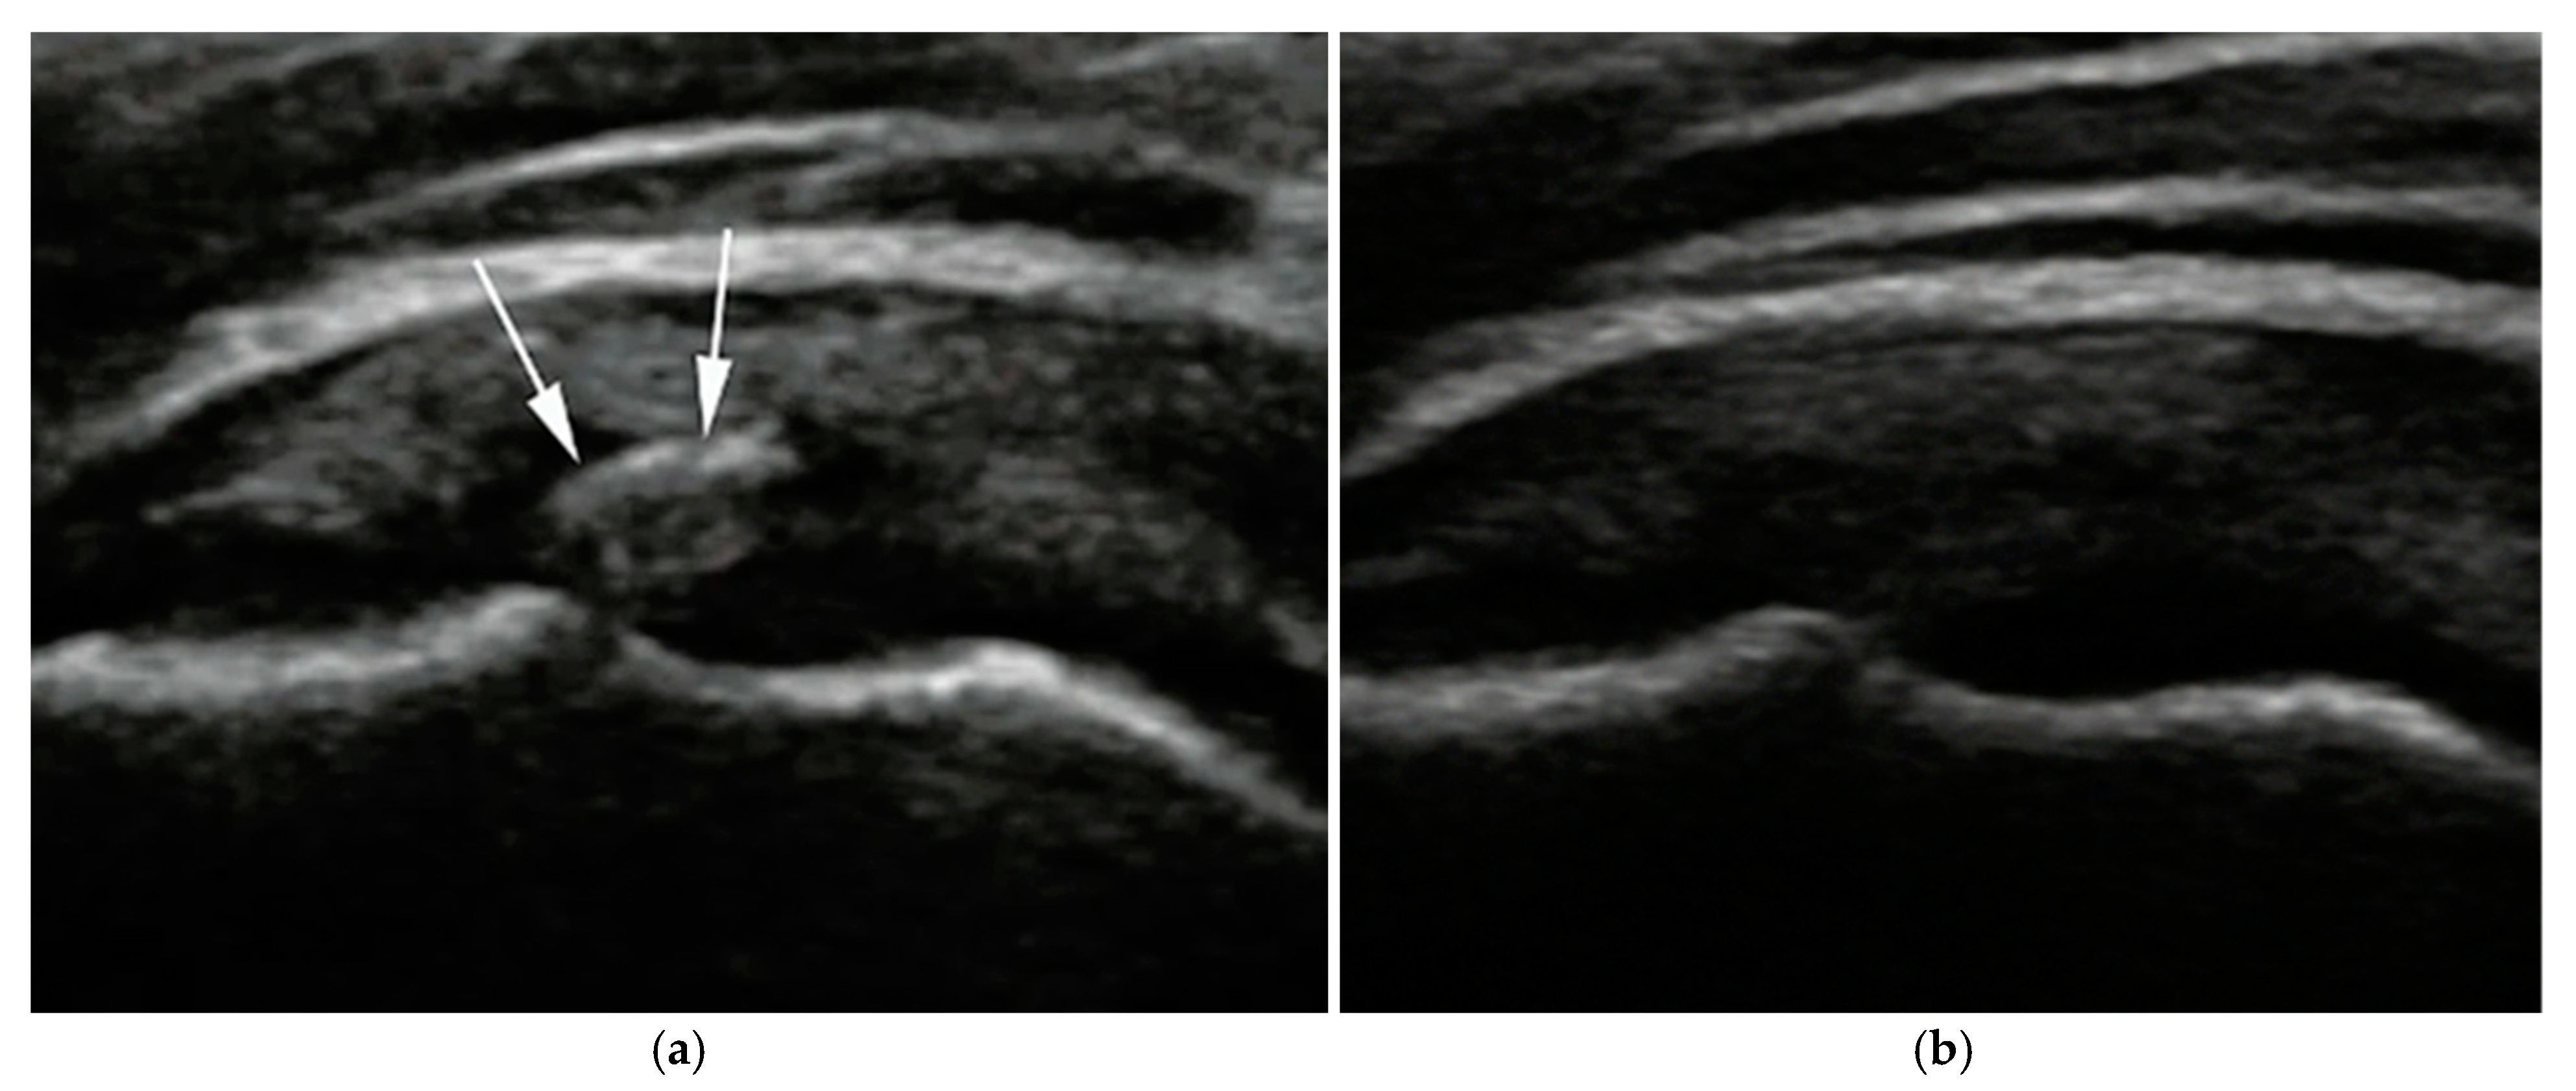

Calcific deposits were most commonly located at the supraspinatus tendon insertion. Follow-up imaging in the ultrasound-guided group revealed echotexture changes and fragmentation consistent with progressive resorption (Figure 3).

Figure 3. Representative ultrasound images of calcific deposits in a patient treated with ultrasound-guided ESWT. (a) Baseline image showing a well-defined calcific deposit (white arrows); (b) Six-month follow-up demonstrating complete resorption, with no visible echogenic material.